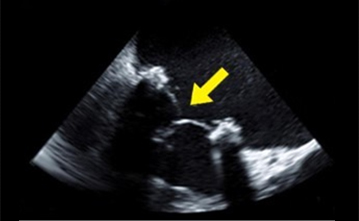

경흉부심초음파와 원리는 동일하나 식도로 초음파 기구를 삽입하여 심장 가까이에서 구조를 살펴보는 검사입니다. 최소한 6~8시간의 금식이 필요하며 검사 직전에 목부위를 마취하고, 수면유도제 등을 사용할 수도 있겠습니다. 경흉부심초음파에서의 이상소견에 대한 정밀한 검사를 요할 때 사용할 수 있는 검사입니다.